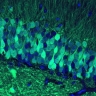

В статье в Science Immunology сотрудники Гарвардского университета пишут о том, что сдерживать ненужную активность иммунной системы помогает блуждающий нерв. Точнее, те нейроны в составе блуждающего нерва, которые называются ноцицепторами. Они воспринимают различные неприятные стимулы – слишком сильное тепло, механические травмы, химическое раздражение и пр. У блуждающего нерва есть много ответвлений в различные органы, в том числе и в лёгкие, и в последнее время стали появляться данные, что его ноцицепторные нейроны задействованы в дыхательных аллергических реакциях и в реакции иммунитета на бактериальную пневмонию. Также известно, что активность этих нейронов меняется при гриппе, и что если их отключить, болезнь будет протекать значительно тяжелее – по крайней мере, у мышей.